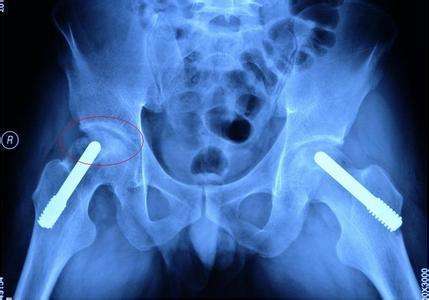

股骨头坏死患者肌肉萎缩主要是因为大腿的血液供应减少造成的。股骨头坏死的发生虽然原因各个有不同,但是发病肌机理都是导致股骨头周围血液循环障碍。

血液循环障碍不但会造成股骨头坏死,同时还会造成骨动脉都下肢广泛组织的血液供应减少,下肢肌肉长时间营养不良,就会造成下肢肌肉萎缩。第二种原因是,患肢大腿由于疼痛不经常走路负重,肌肉长时间得不到有效的锻炼肌肉不再发育,肌肉逐渐萎缩变小,造成的废用性肌肉萎缩。

针对股骨头坏死所导致的肌肉萎缩,其实并非都能恢复。之所以同样是肌肉萎缩,有的人能恢复,有的人不能恢复的问题,主要原因出在股骨头坏死的程度上。中早期股骨头坏死股骨头外形多大的破坏,修复后股骨头外形基本正常,不影响走路功能,将来病人走路距离不受影响,负重也不受影响。同时早期股骨头坏死血液循环破坏也不严重,通过治疗可以恢复,下肢血液供应不受影响,股动脉完全能够满足下肢用血液的需要,这样通过锻炼下肢肌肉萎缩可以恢复。

中晚期股骨头坏死就不一样了,股骨头塌陷严重,股骨头外形无法恢复,髋关节功能无法恢复,行走距离不能达到正常。股骨头周围血管部分消失终身不能恢复,下肢血运循环不能满足肌肉发育的需要,肌肉在缺乏血液营养的条件下不可能正常发育,这样一部分股骨头坏死患者的下肢肌肉萎缩就不可能恢复。